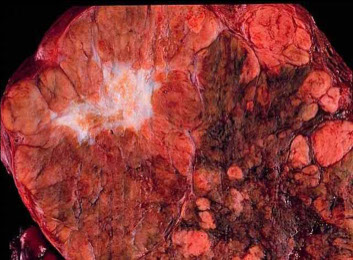

Nutmeg Liver

Liver looks mottled due to bloody congestion in the liver caused by rt-heart failure and Budd-Chiari syndrome

- if persists can cause centrilobular congestion and necrosis resulting in cardiac cirrhosis